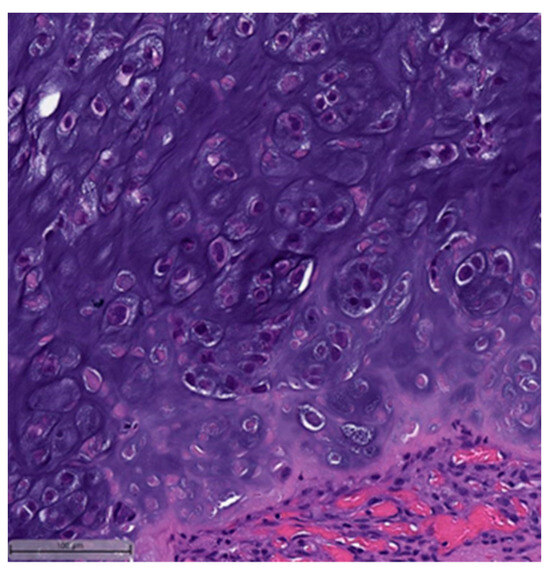

Figure 2. Squamous cell carcinoma component (H&E, 20×).- Spindle cell carcinoma (SpCC) (Figure 3);

Figure 3. Spindle cell carcinoma (H&E, 20×). - Metaplastic carcinoma with heterologous mesenchymal differentiation (MCHMD);